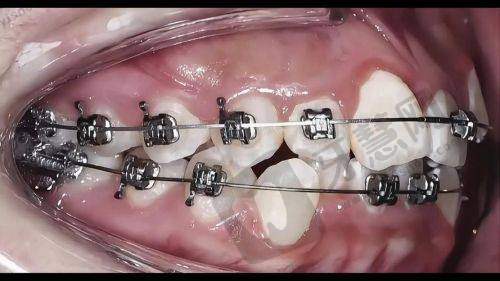

正畸方式选择:该方案提供多种正畸方式。金属托槽矫正价格在 8700 - 15000 元起,是传统且经济的方式,适用于多数牙列不齐病例,通过金属托槽和弓丝配合调整牙齿位置;陶瓷托槽矫正费用约为 12600 - 20000 元起,美观性优于金属托槽,适合对美观有要求的患者;隐形矫正价格区间在 25000 - 40000 元起,采用数字化定制矫治器,几乎隐形、佩戴舒适,患者可自行摘戴,不影响日常生活和饮食;舌侧矫正价格在 43000 - 80000 元起,将矫治器安装在牙齿内侧,完全隐形,但对医生技术要求高。

技术优势:拥有精良正畸技术,医生团队能根据患者具体情况选择更适合的正畸方式,对于复杂牙齿畸形问题,可采用舌侧矫正等高端技术,确保达到至佳矫正成效。

长春现代口腔快速正畸方案 29200 元起顾客实例

小李是年轻上班族,牙齿牙列不齐影响自信心,选择长春现代口腔快速正畸方案 29200 元起,医生为其制定陶瓷托槽矫正方案,正畸过程中定期检查和调整,小李严格按要求佩戴牙套和注意口腔卫生,牙齿逐渐变整齐,面部美观度提升,他对治疗成效满意,觉得价格划算。小张是学生,牙齿地包天,接受该方案治疗,医生采用金属托槽矫正方式,经过两年多矫正,地包天问题明显改善,咬合功能修复正常,他表示医生和护士特别关心他,感受到专精和温暖。这些实例表明该方案能有效解决牙齿畸形问题,在价格、成效和服务等方面获顾客认可。